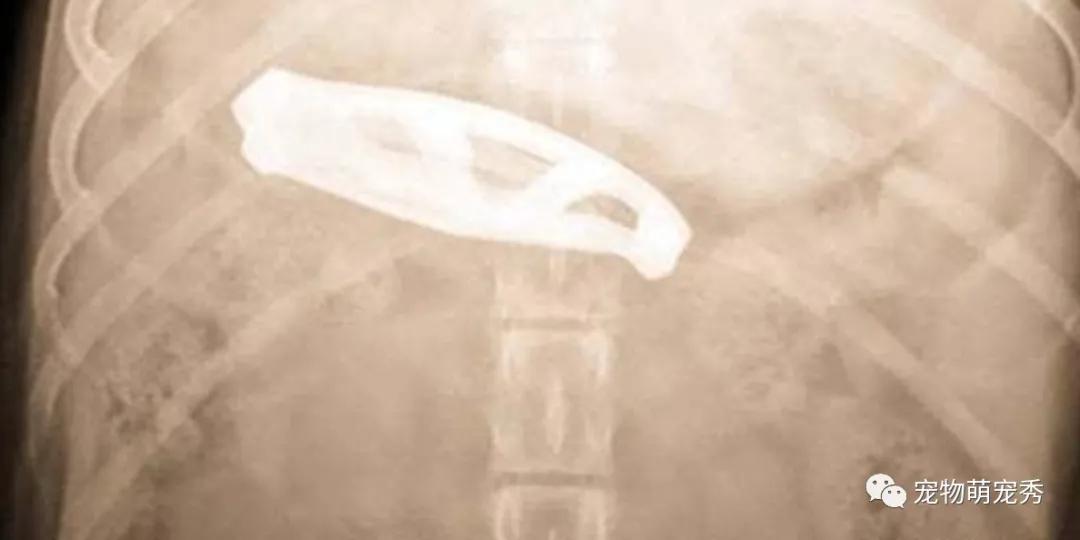

▲接着医生通过手术取出了水果刀,狗狗也没有什么大碍,正在康复中,好好休养就可以。